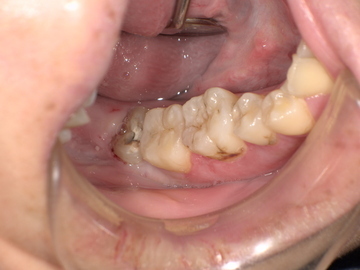

Before(下親知らずの抜歯前) 虫歯のある状態で埋まっている親知らず 抜歯前の骨の状態のレントゲン像

拝見したところ、一部分のみ生えている右下の親知らず(第3大臼歯/8番)と右下の奥歯(第2大臼歯/7番)との間で、歯肉の腫れが認められました。

原因をより詳しく調べるためパノラマレントゲンを撮影したところ、右下の親知らずは骨の中に埋まった状態のまま虫歯になり、隣接する歯を押しており、接触している奥歯の骨が溶けてしまっています。 そのため、右下の親知らずと隣の奥歯の間には、歯と歯ぐきの境目の溝である「歯周ポケット」が通常よりもかなり深くなっていました。

以上の点から、痛みの原因は、虫歯により深くなった歯周ポケットの中で歯垢が溜まって細菌が繁殖し、親知らず周囲の歯ぐきに炎症が起きる「智歯周囲炎」であると診断しました。